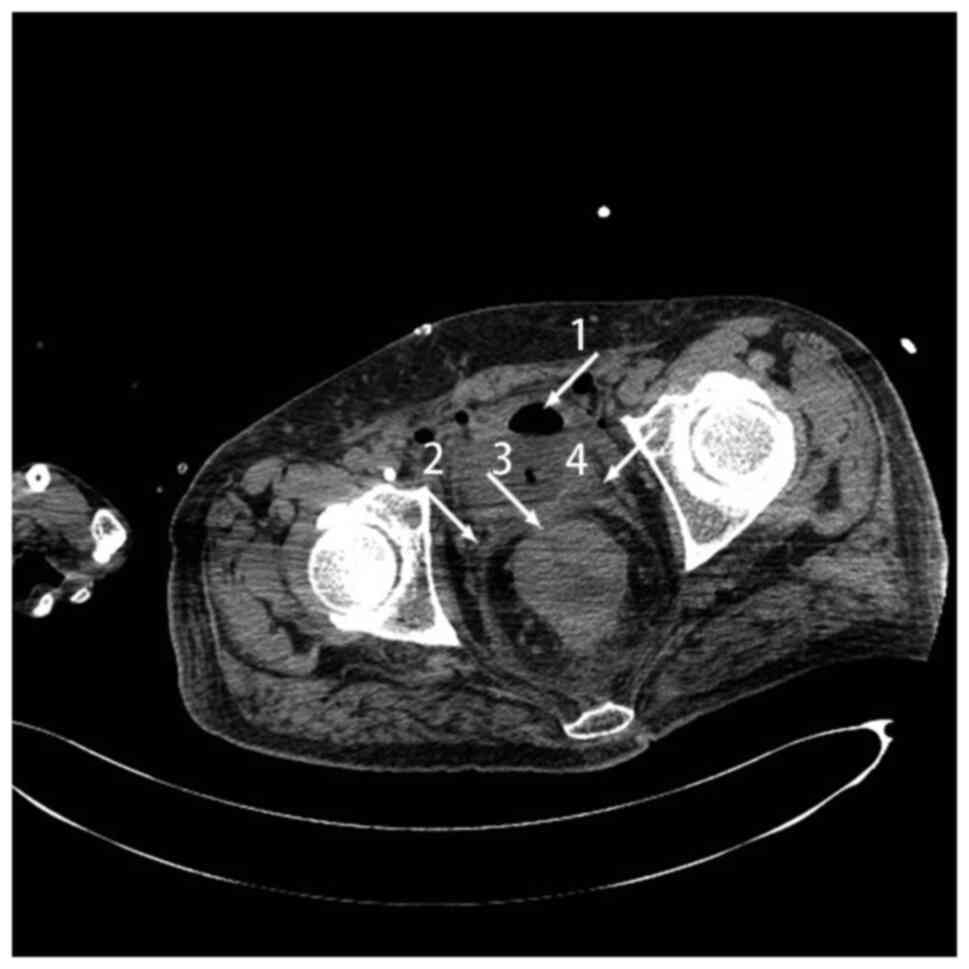

Figure 2.

Computed tomography scan showing air in the bladder (arrow 1), irregular thickening and enhancement of the sigmoid in the distal parts of the sigmoid colon and proximal parts of the rectal wall (arrows 2 and 4), and a fistula between the colon and bladder (arrow 3).

A 55-year-old man presented to the Affiliated Hospital of Yangzhou University in December 2020 with urinary frequency, urgency and pain that had persisted for 4 months. The patient had a background of sigmoid cancer. On presentation, the patient was afebrile with normal vital signs. A routine blood test showed a neutrophil level of 87.1×109 g/l (reference range, 0.04-0.5 ×109 g/l), a hemoglobin level of 84×1012 g/l (reference range, 120–160 g/l). A routine urine test showed a red blood cell level of 3/HPF (reference range, 0–3/HPF) and a white blood cell level of 139.8/HPF (reference range, 0–5/HPF). The urine culture found Escherichia coli, and the fecal occult blood test was positive. CT showed sigmoid cancer with invasion and a fistula in the bladder wall. Cystoscopy revealed hyperemia, edema and thickening in the bladder wall. Colonoscopy confirmed colon cancer (Fig. 4). The patient was treated with 0.5 g levofloxacin, once a day for 10–14 days. Due to the patient's good physical condition and a lack of obvious manifestations of inflammation or intestinal obstruction, a laparoscopic palliative sigmoidectomy and a partial cystectomy were performed. The diagnosis was colon cancer with a CVF. The patient remained asymptomatic after 10 months.

Computed tomography showing air in the bladder (arrow 1), thickening in the sigmoid colon, rectum and bladder wall (arrows 2 and 4), and a fistula between the colon and bladder (arrow 3).